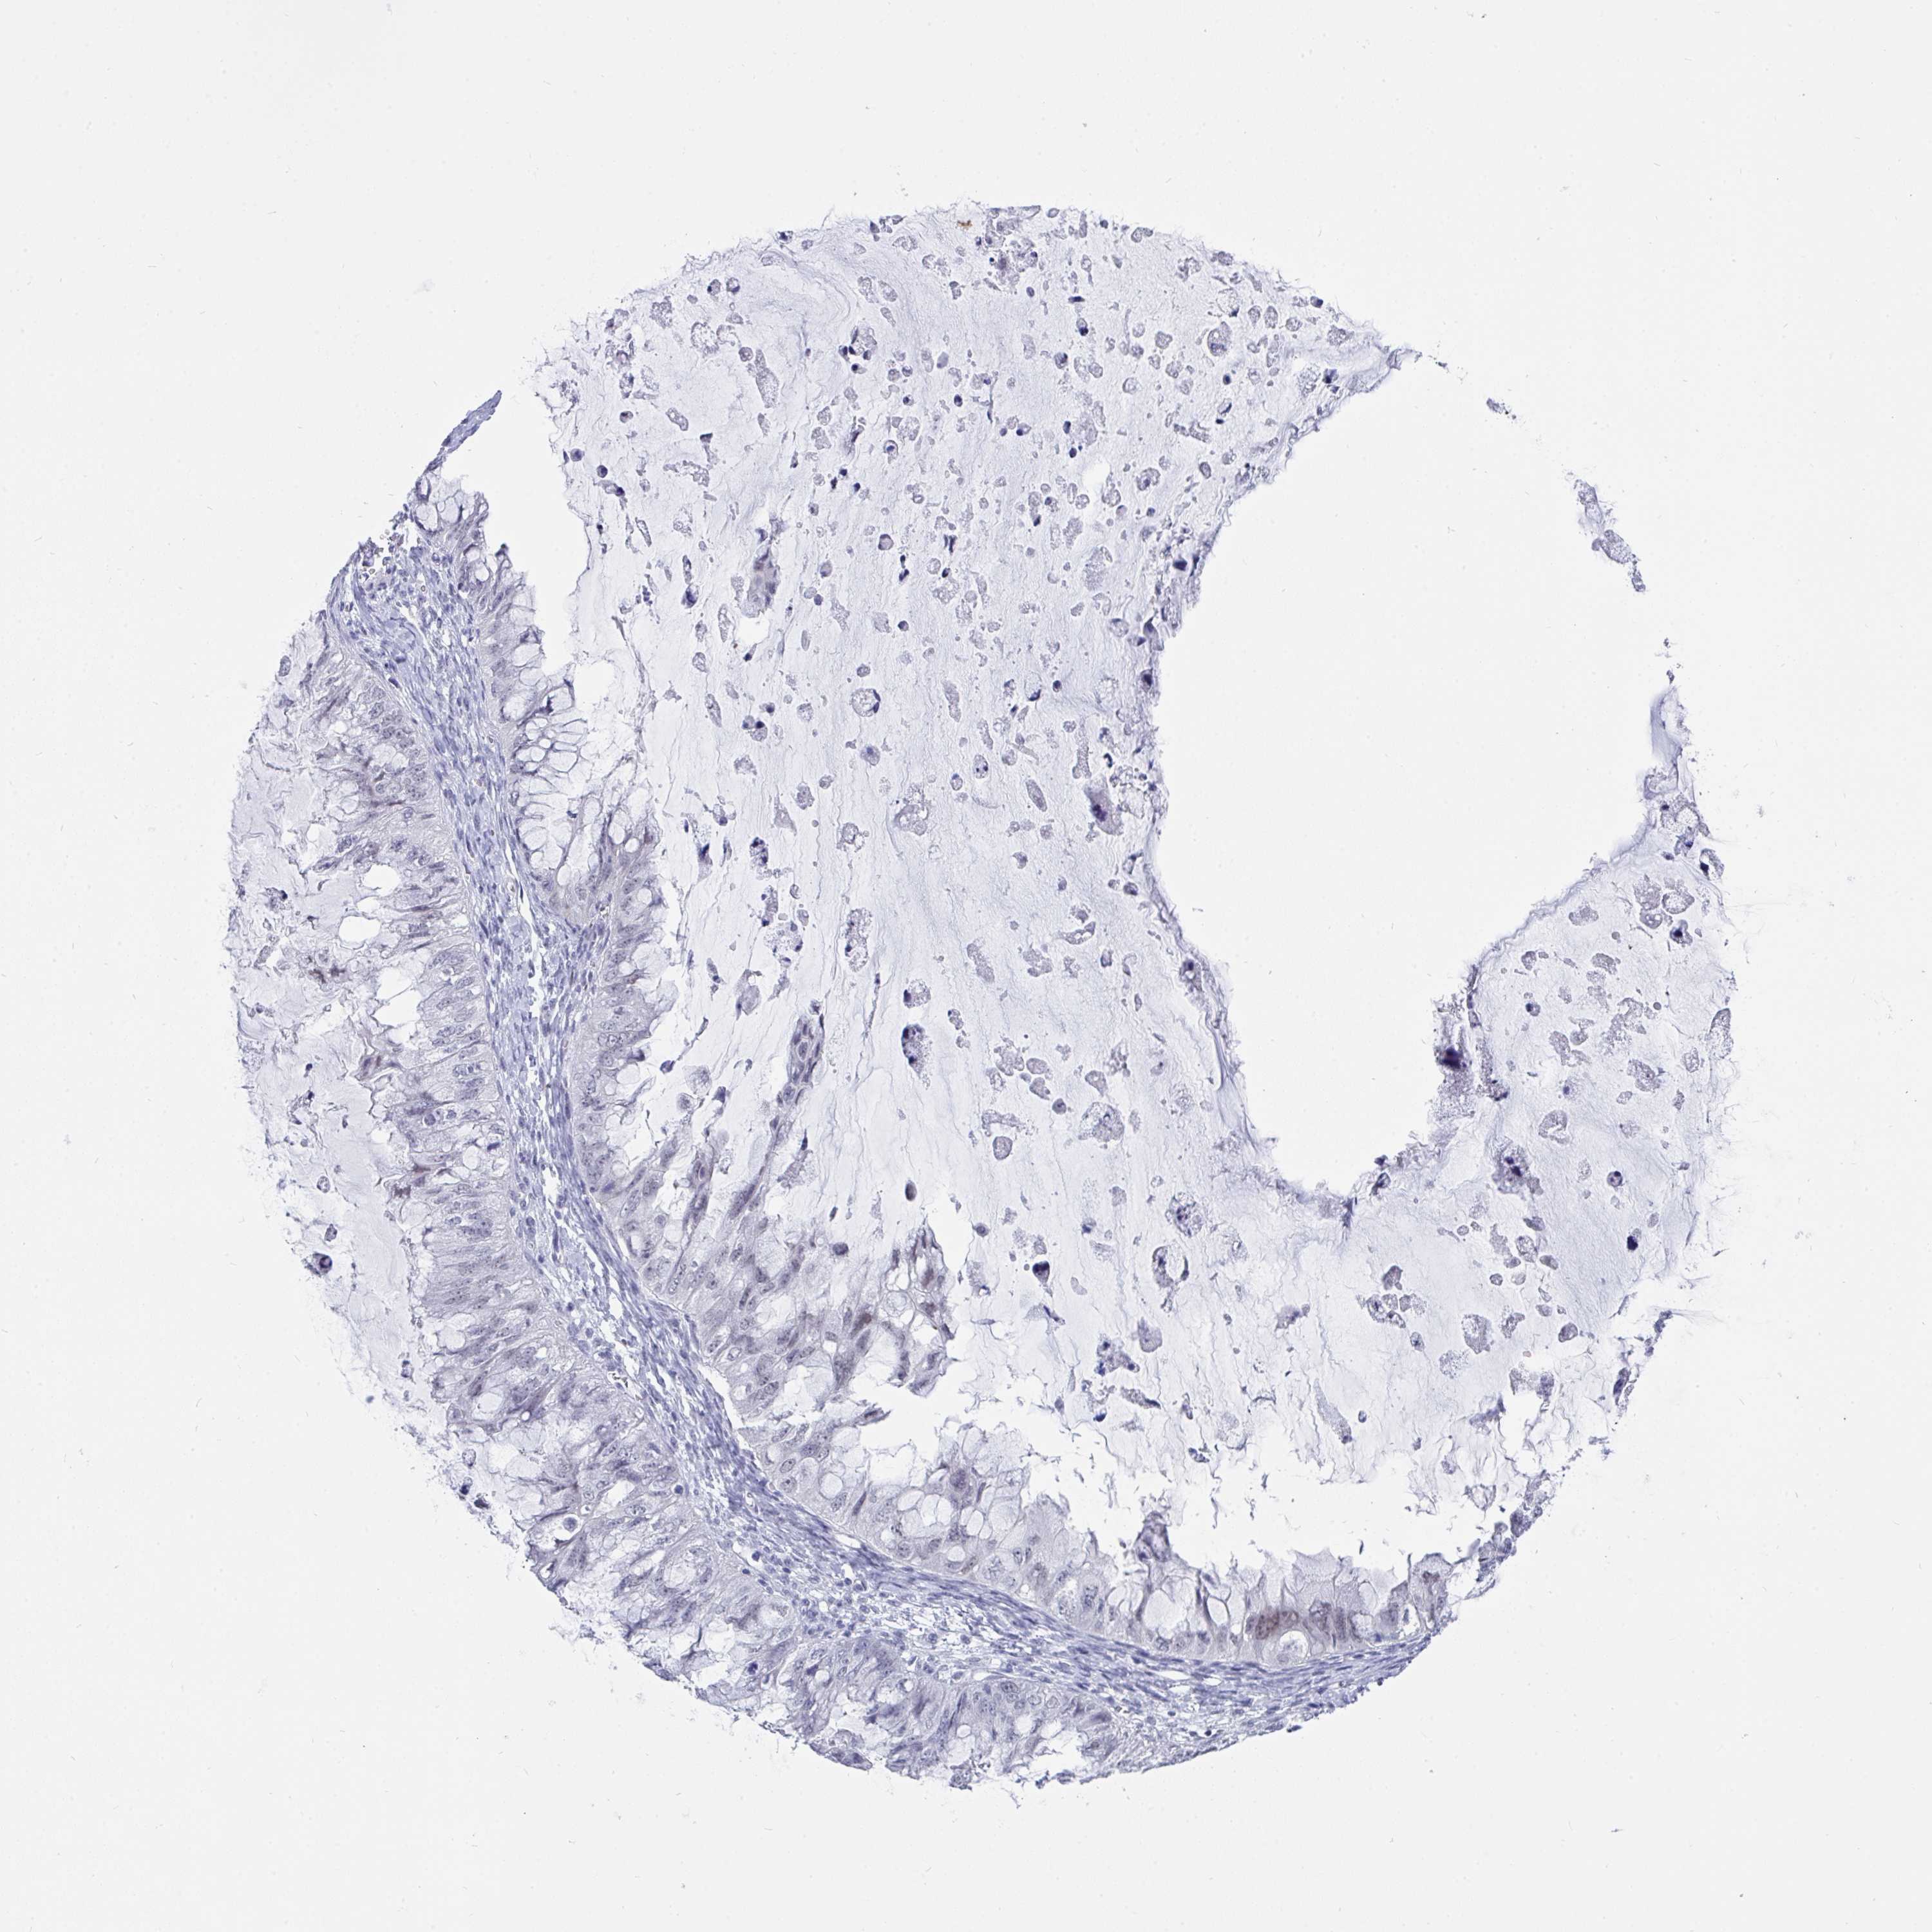

OVARIAN CANCER - Protein expressioni

A mouse-over function shows sample information and annotation data. Click on an image to view it in a full screen mode. Samples can be filtered based on level of antibody staining by selecting one or several of the following categories: high, medium, low and not detected. The assay and annotation is described here.

Note that samples used for immunohistochemistry by the Human Protein Atlas do not correspond to samples in the TCGA dataset.

Antibody stainingi

Antibody staining in the annotated cell types in the current human tissue is reported as not detected, low, medium, or high, based on conventional immunohistochemistry profiling in selected tissues. This score is based on the combination of the staining intensity and fraction of stained cells.

Each image is clickable and will lead to virtual microscopy that enables deeper exploration of all samples and also displays staining intensity scores, fraction scores and subcellular localization as well as patient and tissue information for each sample.

Antibody HPA047624

Antibody HPA054627

Cystadenocarcinoma, serous, NOS

Carcinoma, NOS

Cystadenocarcinoma, mucinous, NOS

Carcinoma, endometroid